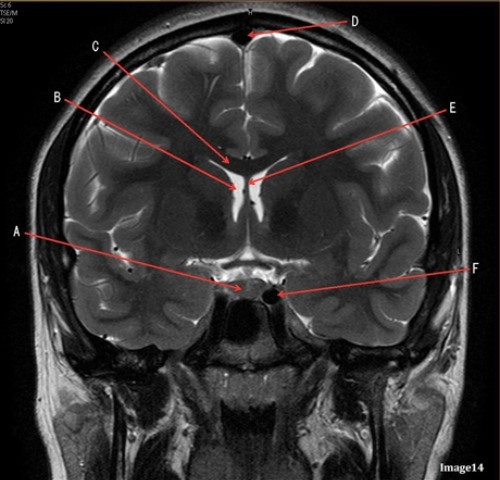

Letter A in image 14 is pointing to:

A. Corpus callosum

B. Third ventricle

C. Lateral Ventricle

D. Pituitary gland

E. Fornix

Letter F in image 14 is pointing to:

A. Third ventricle

B. Pituitary gland

C. Hypothalamus

D. Internal carotid artery

Image 11 is an example of a _______ weighted sequence acquired in the _______ scan plane.

A. T1; Axial

B. T1; Coronal

C. T2; Axial

D. T2; Coronal

E. STIR; Axial

Letter E in Image 14 is pointing to:

Letter D in Image 14 is pointing to:

A. Tentorium

B. Sphenoid sinus

C. Frontal Sinus

D. Sagittal sinus

Letter B in Image 14 is pointing to:

Letter C in Image 14 is pointing to: